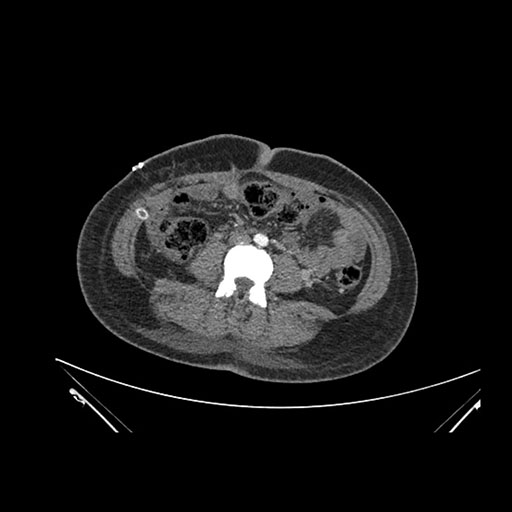

Imaging Analysis

Look through the patient's CT scan to identify any areas of concern for the necessary procedure.

Axial Arterial